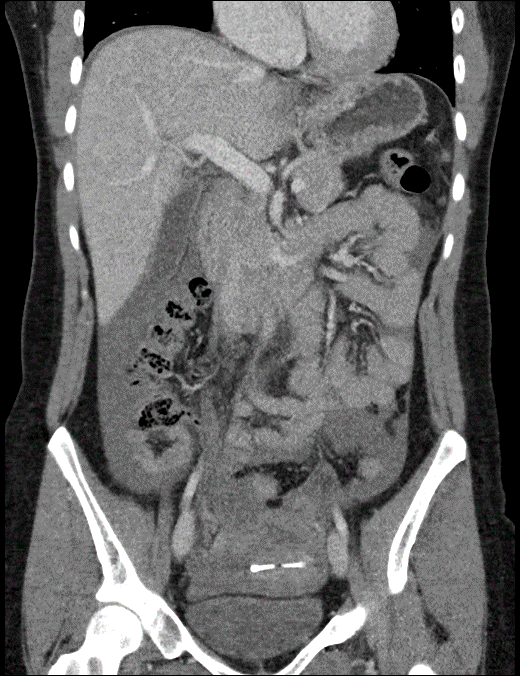

CASE 2: Coronal CT shows large hemoperitoneum.

30 year old female with acute onset pain that radiates to her shoulders. Abdomen tender on exam, UPT negative. CT scan obtained, shows large hemoperitoneum with dense clot in the pelvis. Hard to separate clot from the uterus.